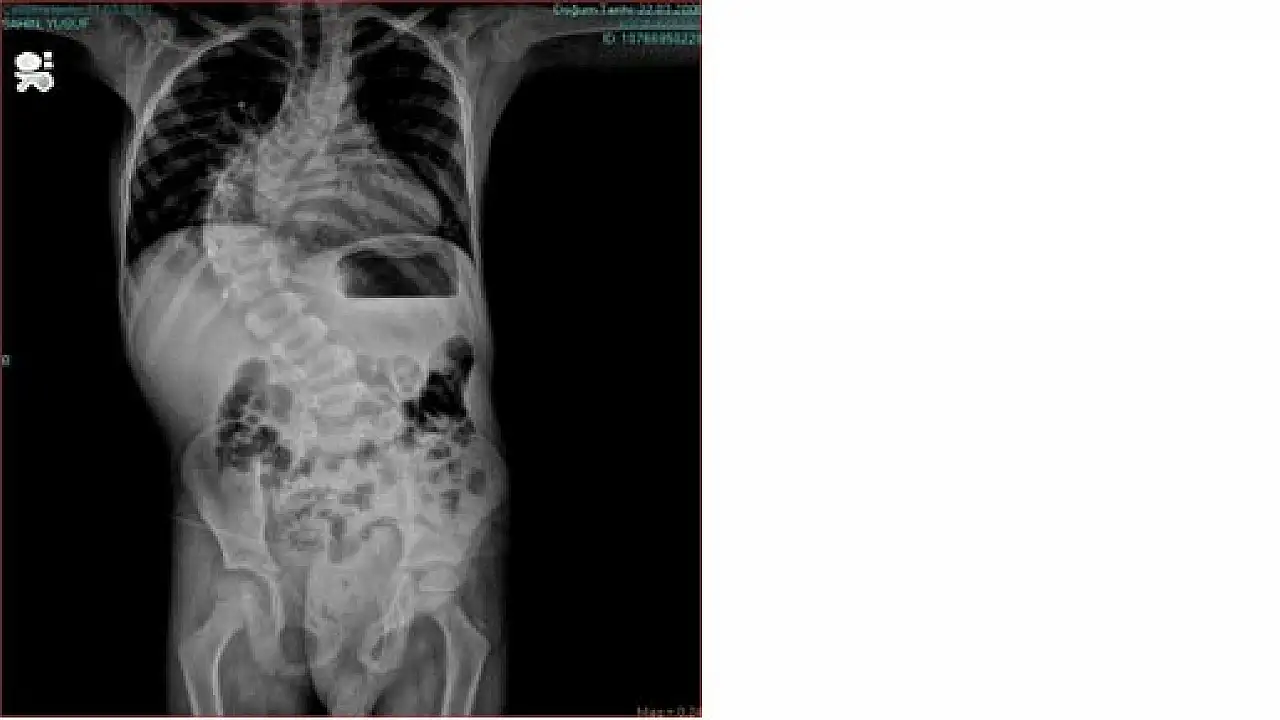

Samsun'da Medical Park Hastanesi’nde skolyoz (omurga eğriliği) tedavisi gören 7 yaşındaki Yusuf Şahin, Türkiye'de yeni yapılmaya başlanan, omurga eğriliği için yeni geliştirilen ameliyat tekniği ile operasyona alındı. Ortopedi ve Travmatoloji Uzmanı Prof. Dr. Nedim Karaismailoğlu tarafından başarılı bir şekilde gerçekleştirilen 4 saatlik bir operasyon ile 20 cm uzunluğunda "uzayan platin" adı verilen bir alet takıldı.

Karadeniz’de bir ilk olan ve Samsun Medical Park Hastanesi’nde yeni başlanan skolyoz ameliyat tekniği hakkında bilgi veren Ortopedi ve Travmatoloji Uzmanı Prof. Dr. Nedim Karaismailoğlu, omurga eğriliği tedavisi gören hastaların her 6 ayda bir, 6 saat süren ameliyata girdiğini, yeni geliştirilen bu yöntem ile 4 saatlik operasyon sonucunda hastaların sağlıklarına kavuştuklarını söyledi. Bu tekniğin Türkiye'de son 6 aydır uygulandığını, Karadeniz'de bir ilk olduğunu ifade eden Prof. Dr. Nedim Karaismailoğlu, “Bu yeni yöntem hem çocuğun büyümesine müsaade ediyor hem eğriliğin giderek azaltılmasını müsaade ediyor. Tekrar ameliyata gerek olmadan 3 ayda bir hasta geliyor. Bir makine yardımı ile içteki parçanın uzaması sağlanıyor ve çocuğun konforu artıyor. Bu yöntem, hastalar için umut ışığı oldu" dedi.